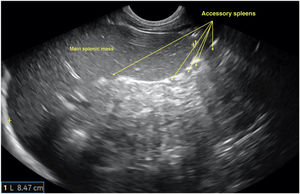

An abdominal ultrasound scan revealed hepatomegaly with periportal hypoechogenicity around the main portal vein and its branches (Figs. 1 and 2), and mild splenomegaly with multiple accessory spleens in the hilum (Fig. 3). The patient was referred to the corresponding referral hospital due to suspicion of myeloproliferative disease, where he received a diagnosis of acute myeloid leukaemia.

Oblique longitudinal plane of the left hypochondrium obtained with a convex probe at the level of the epigastrium, showing: a) Hepatic parenchyma at the level of the left lobe (LHI) with transversal sections of echo-poor periportal haloes of larger (M) and smaller (m) size; b) Enlargement of previous image with measurement of the diameter of one of the periportal haloes. Stomach (E).